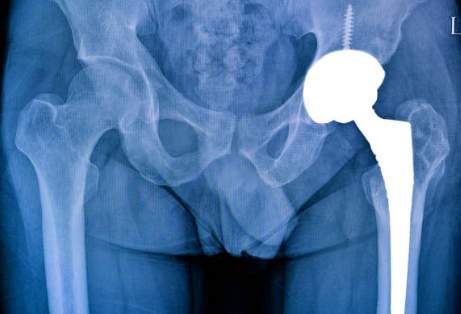

1. 고관절 골절 치료방법- 수술이 필요합니다.

대부분의 고관절 골절은 수술적 치료가 필요합니다. 수술의 목적은 골절 부위를 안정화하고 다시 정상적으로 돌아가게 하는 것입니다.

수술 방법은 골절의 위치와 형태에 따라 다를 수 있습니다. 종종 고관절 인공관절 교체 수술이나 고관절을 안정적으로 고치기 위한 다양한 수술적 절차가 사용됩니다.